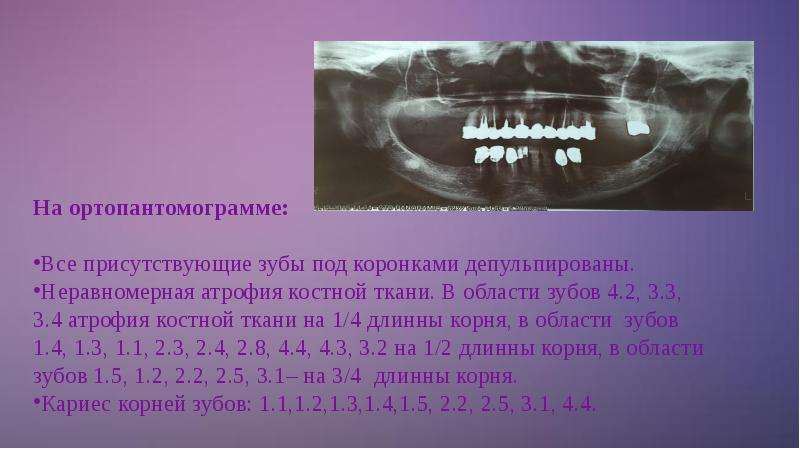

Раздел: Кадры-подсказки